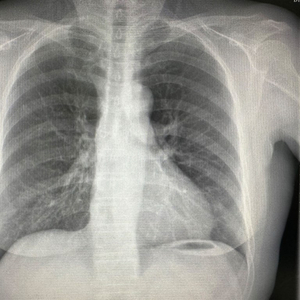

来到华东医院就诊后,医生建议王阿姨做个普通X线平片检查(图1),看看是否肋骨骨折。

图1王阿姨的胸片

拍过平片后,医生没有发现明显的肋骨骨折,于是开了些药膏,让她回去静养随访。